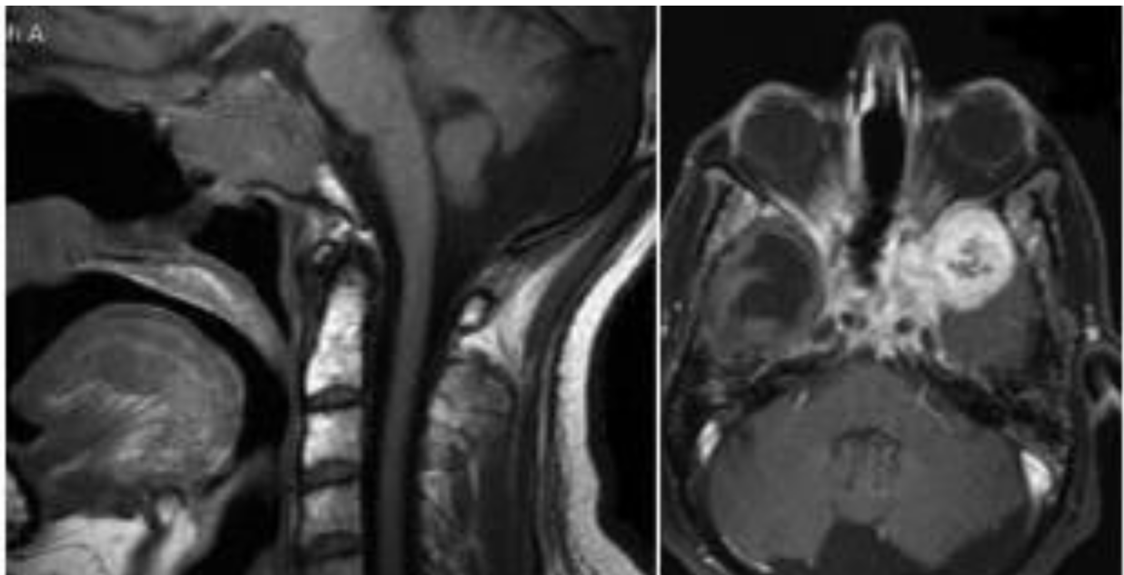

患者40+岁,女性,患者临床症状明显,近1年多来相继头痛、复视、肢体无力、吞咽困难等,当地医院诊断为较大斜坡脑膜瘤,辗转多地医院均告知肿瘤无法全切,术后并发症风险发生率高,后慕名咨询德国国际神经科学中心INI寻求巴特朗菲手术治疗,肿瘤切除97%以上,无相关手术并发症。

术前MR示:斜坡较大脑膜瘤,压迫脑干、颅神经,侵犯基底动脉等

术后MR显示:肿瘤近全切除,术后未见脑血肿、脑水肿,神经血管、脑干等组织保护完好。